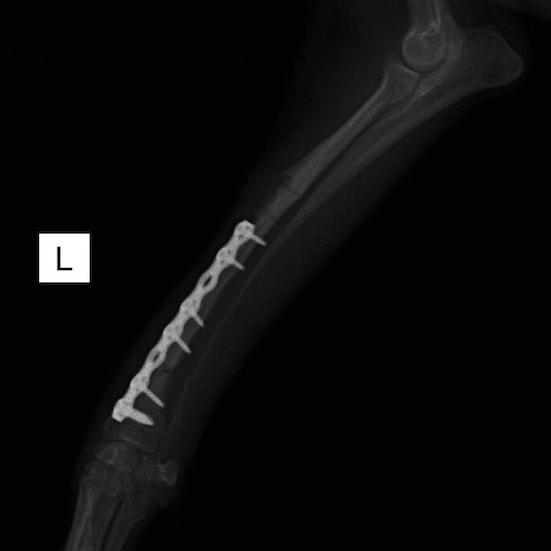

脛骨骨折 : 症例1 | 症例2 | 症例3 | 症例4 | 症例5

Advanced Locking plate system と Locking compression plate system

当院ではAdvanced Locking plate system(ALPS)と、Locking compression plate system(LCPS)という骨接合法で骨折症例の治療を行っています。

Locking Compression Plate

LCPは、スクリュー(ネジ)とプレート(金属の板)をロックする特殊な構造により骨折部位を固定する新しい世代のプレートシステムです。ひとつのホールでロッキングスクリューとスタンダードスクリューの使用を選択できるユニークな構造をしているため、骨折断端間の圧迫を目的とした従来型プレート固定法に加え、高い角度安定性を有するロッキングスクリューを用いた固定法の選択が可能です。従来のプレートシステムでは困難だった部分の骨折や癒合不全の症例に高い治療効果をもたらします。